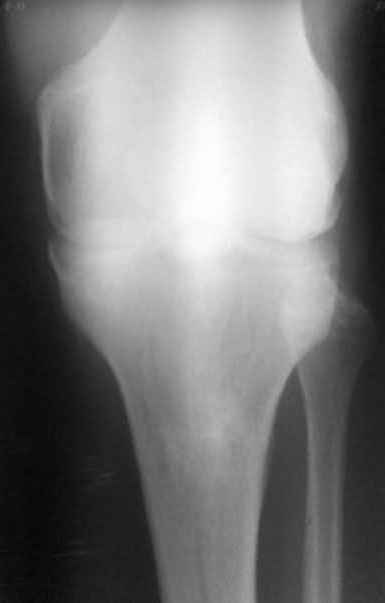

Доктора, предлагаю обсудить клинический случай.

Мужчина 1960 гр в возрасте 10-12 лет получает травму, которую сейчас описать точно не может, не помнит.

В настоящий момент единственная, как ни странно, жалоба –

появление кисты Бейкера. А еще больше косметический дефект.

Собственно, с идеей коррекции косметического дефекта пациент к нам и

обратился.

По видимому, тогда было повреждение задней крестообразной связки,

рекурвация голени стала устойчивой, плато имеет неправильный угол

наклона, а в верхней трети большеберцовой кости формируется маршевый

перелом.

Объективно. Боли при пальпации нет, движения практически в полном

объеме. Рекурвация внешне совершенно очевидная. Положение голени

устойчивое.

Растущая киста Бейкера говорит о начале декомпенсации со стороны

сустава, как я понимаю.